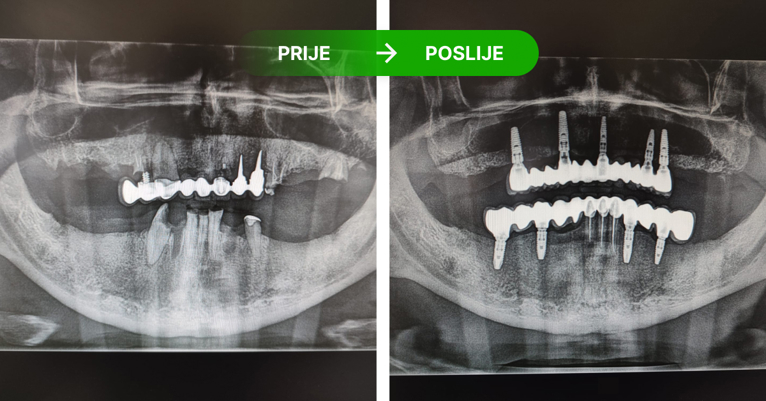

Zubni implantati su titanski vijci koji se ugrađuju u kost kao zamjena za korijen zuba, jednog ili više zuba. Pristup je individualan ovisno o RTG snimci i preostalom broju zuba. Nije potrebno brusiti susjedne zube, već ugrađujemo implantat. Ugrađujemo implantate Nobel Biocare. Ako se održava kvalitetna higijena i kontrola RTG snimanjem implantati traju doživotno, a njihovom ugradnjom zaustavlja se resporbcija kosti.

Dentalni implantati ugrađuju se u čeljust i njihovo učvršćivanje traje 3 do 4 mjeseca – kontrolira se rendgen slikom.

Postupak se izvodi u lokalnoj anesteziji i potpuno je bezbolan. Ukoliko je potrebo ugraditi više implantata, ugrađuju se istovremeno u jednoj posjeti. Nakon 3 do 4 mjeseca vrši se kontrola učvršćivanja i pristupa se izradi keramičkog mosta ili krunice.